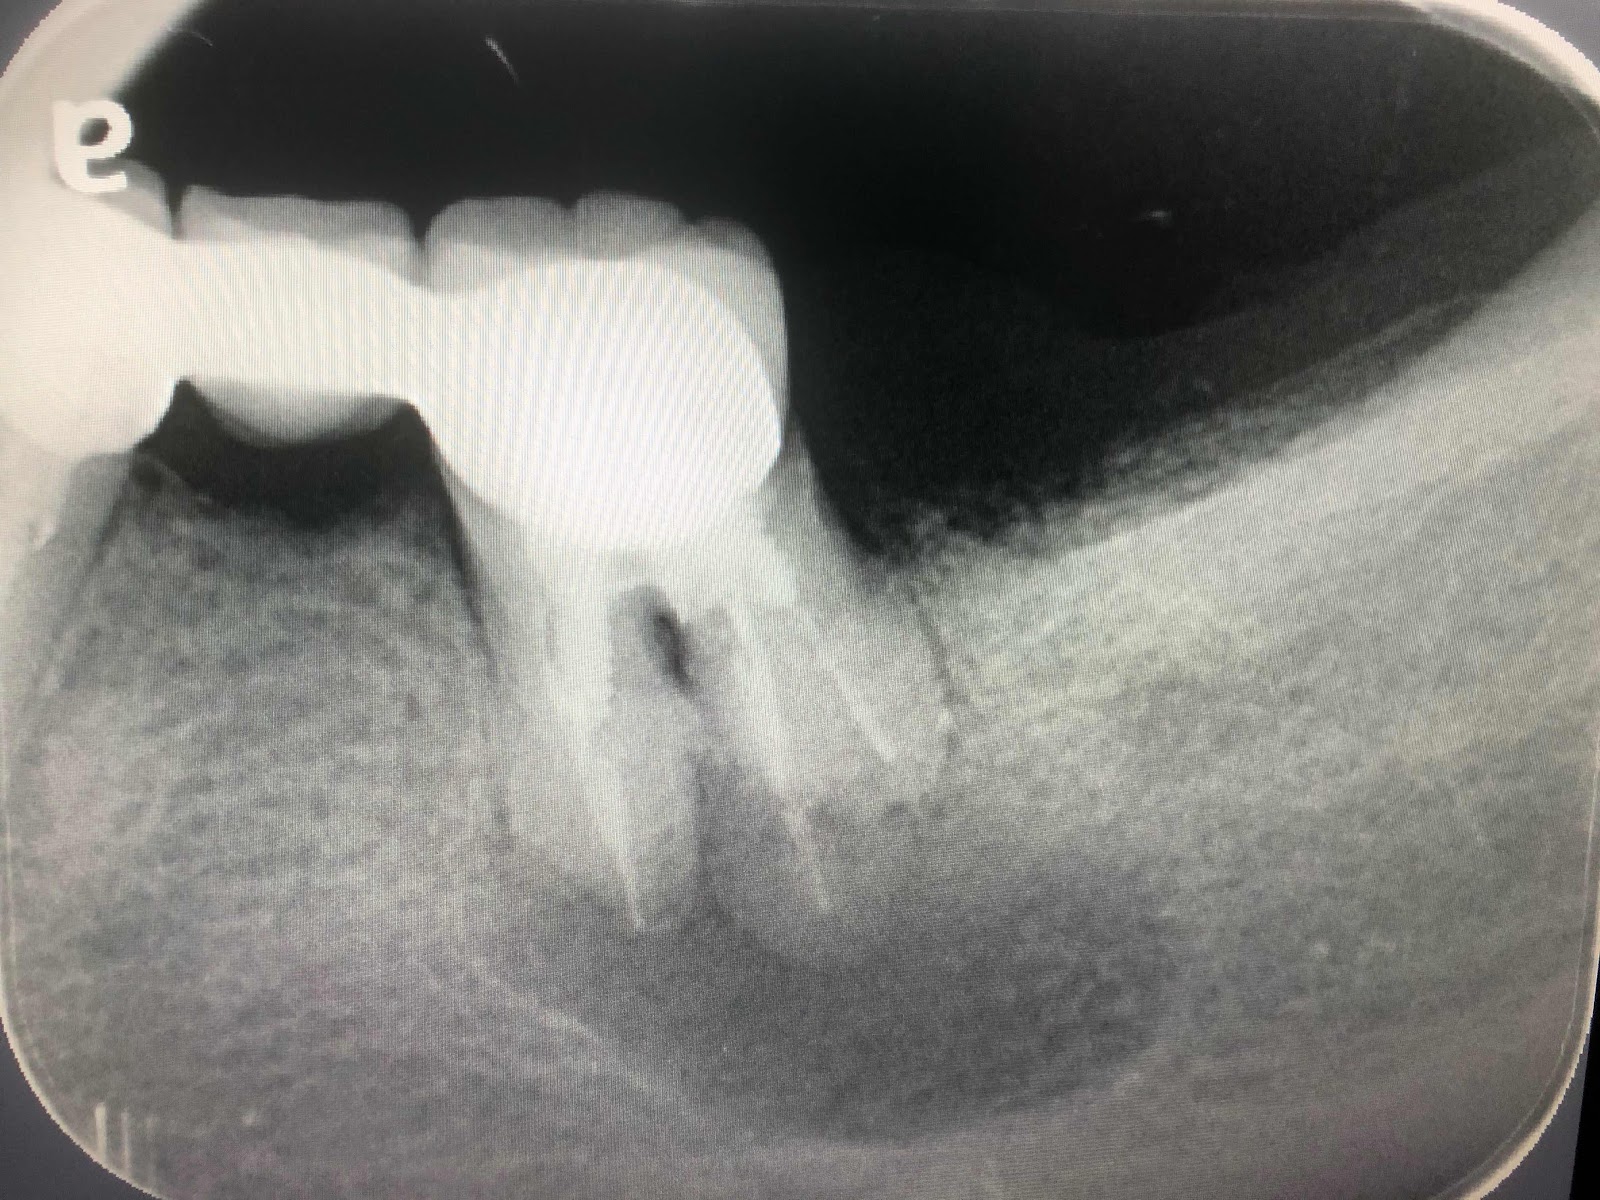

以下我將以前幾天所做的case 為大家說明為何時間浪費

這案例需要拆除牙套,拆除牙釘(根管專),根管再治療(根管專),拔除跟尖膨大的困難拔牙(口外專),可繼續使用的牙齒需要做牙冠增長手術(牙周專),無牙區日後需要植牙(植牙專或牙周專)與植體膺復(膺復專),或是活動假牙(膺復專),看起來需要經歷兩個禮拜,轉手四位醫師才能完成初步治療,可是在一位通才(能力在80%以上)醫師手上只要一個小時一個診次完成,差異極大!

拆牙套拆釘 根管治療

拔除膨大牙根

傷口處理與牙冠增長手術